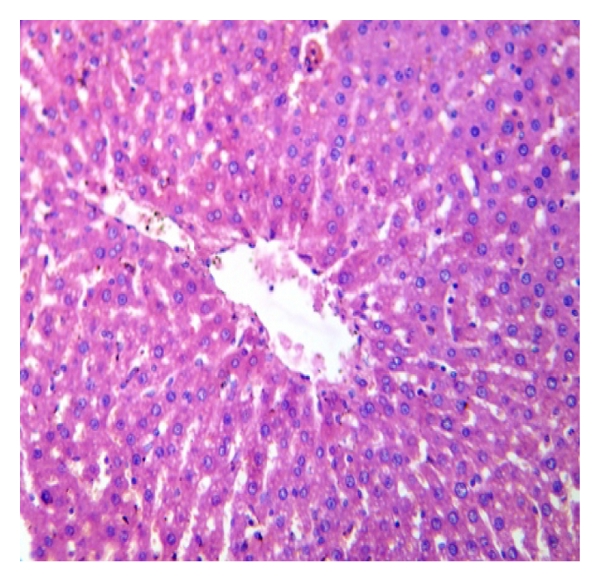

3.3. Histopathological Procedures

The histological sections of the control and extract treated groups are represented in Figure 6. There were no detectable changes in cellular morphology of hepatocytes. The hepatic architecture was normal with well-defined central vein. No necrosis, steatosis, chronic inflammatory infiltration, or degenerative changes were observed in any of the extract treated animals. The biochemical and histopathology results of leaf and bark extracts are comparable, and the reason for these similarities may be that the samples are from the same plant. The preliminary investigation on the presence of phytochemicals in the extracts of A. altilis leaf and bark parts revealed that maximum phytochemical constituents were present in methanol extracts of both AL and AB. Terpenoids and triterpenoids were present in all solvent extracts of AL and AB. Saponins and tannins were present in aqueous extracts, while steroids were present in petroleum ether, benzene, and methanol extracts of AL and AB [21].